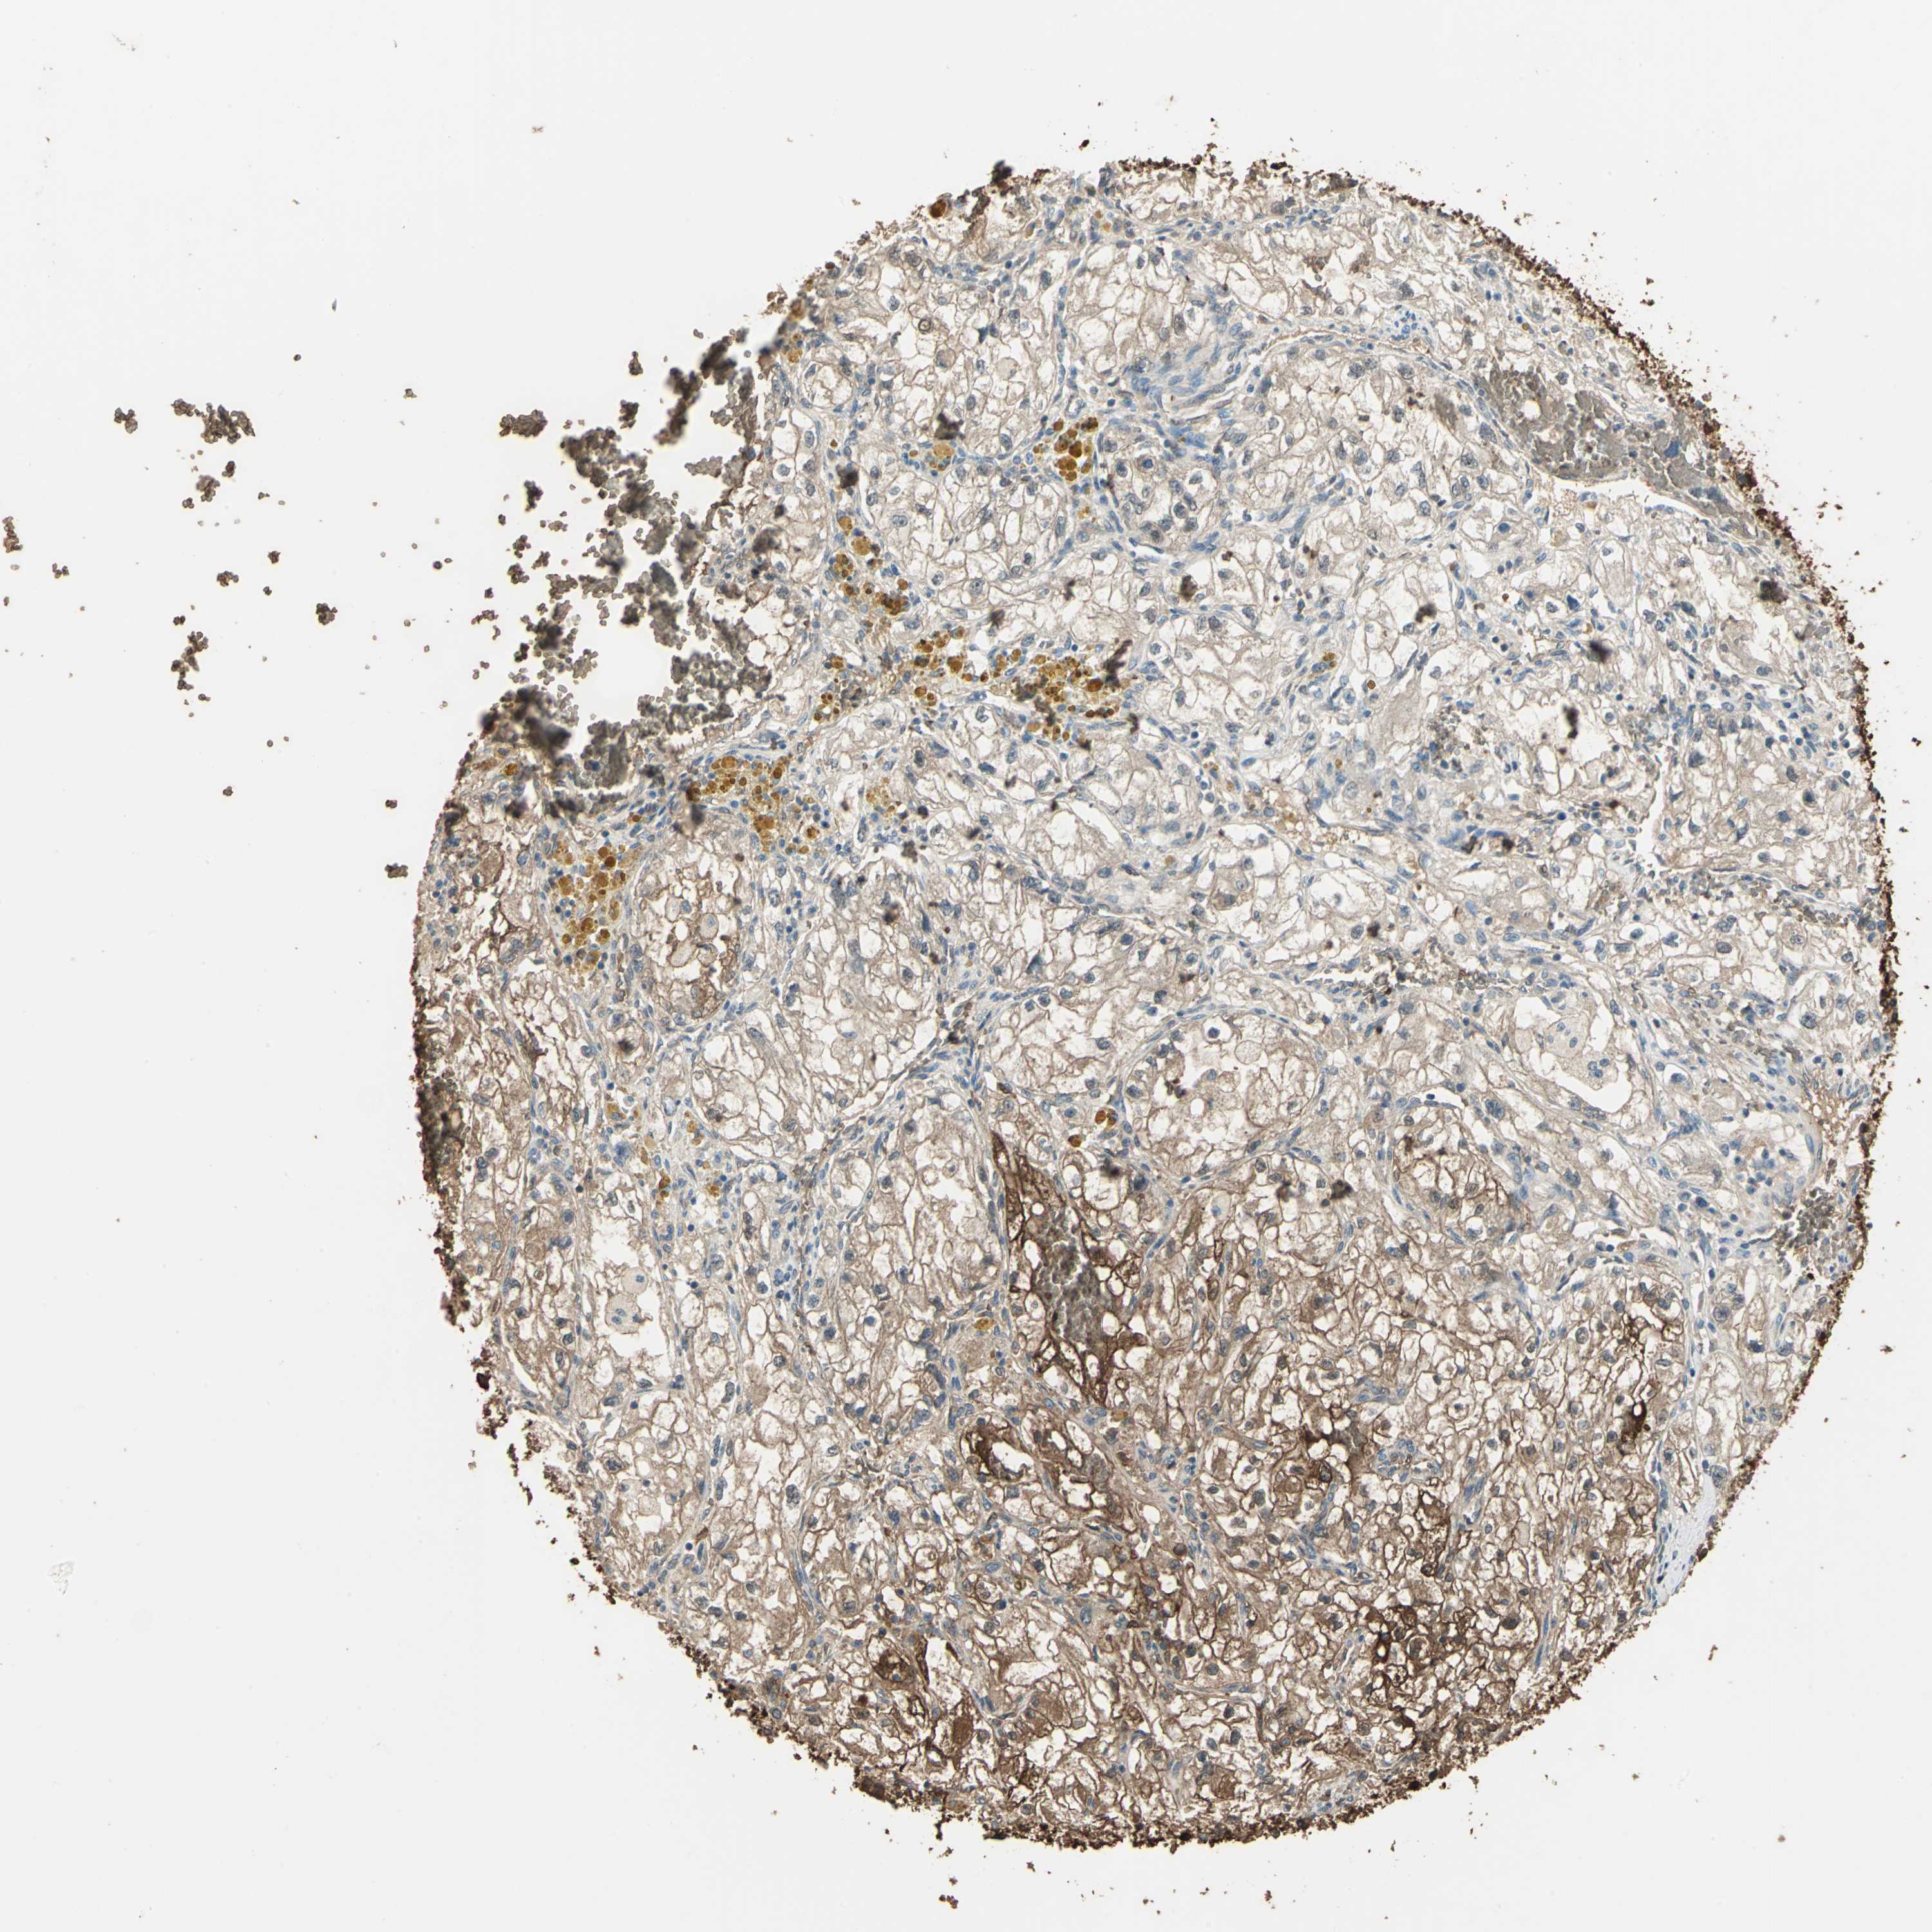

CANCER RENAL CANCER Show tissue menu

KICH TCGA KIRC TCGA KIRC VALIDATION KIRP TCGA PROTEIN RCC CPTAC PROTEIN EXPRESSION

Renal cancer

Kidney renal clear cell carcinoma

DDAH1 is validated prognostic, high expression is favorable in Kidney Renal Clear Cell Carcinoma (validation)

: 69.55

Average pTPM 72.4

Number of samples 100